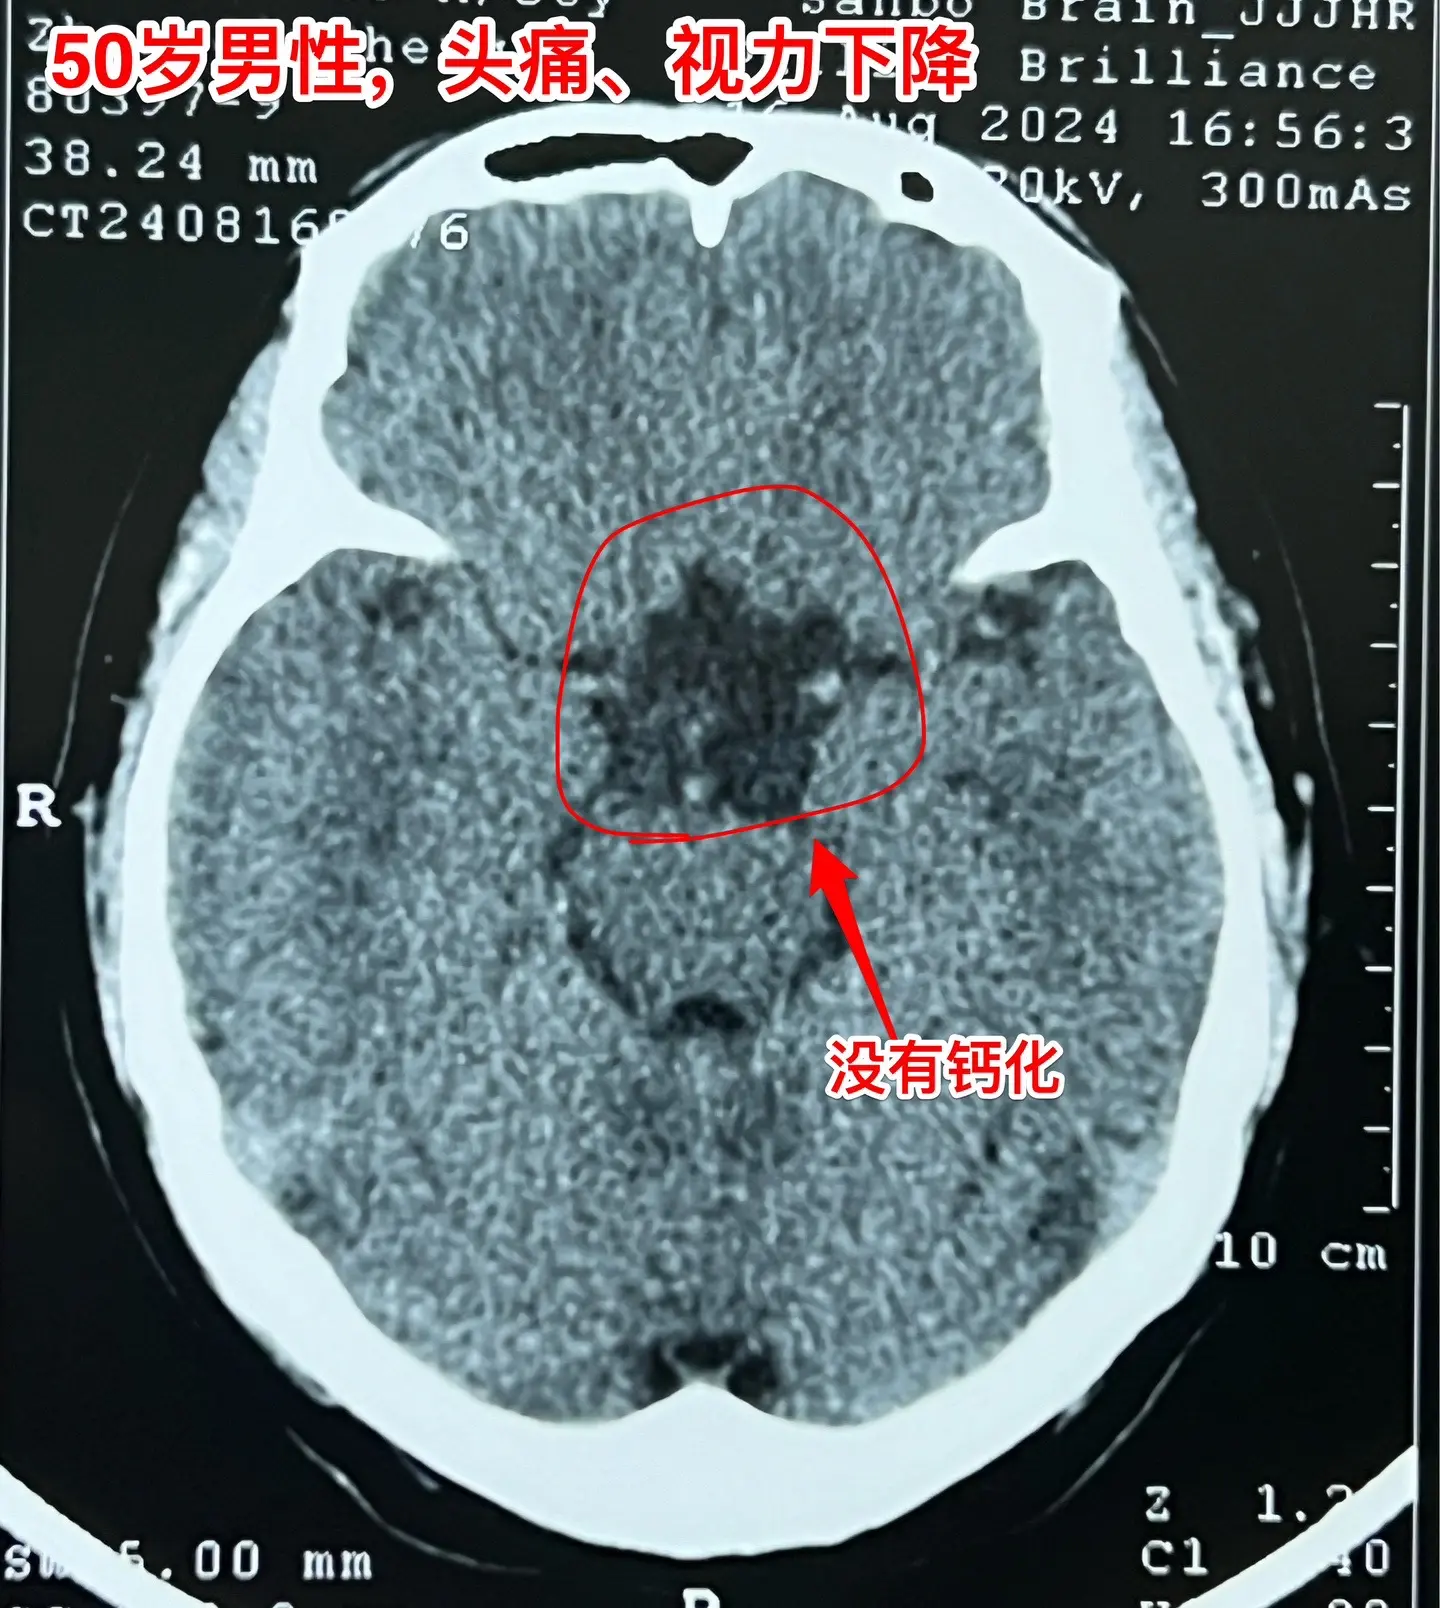

颅咽管瘤手术,出院3天就开车,合适吗?50岁的山东临沂男性,因头痛一年,左眼视力下降三个月于2024.8.16在我科住院。左眼视力0.1,右眼视力1.0。8月22日行开颅手术切除颅咽管瘤,手术后视力改善,身体恢复顺利,9月2日出院了,出院前测左眼视力0.5,右眼1.0。出院时精神好,体力好。 9月8日患者女儿和我联系,说患者出院三天就开车了。我告诉她,需要复查视力和视野,如果视野有缺损,开车是有风险的,不适合开车。